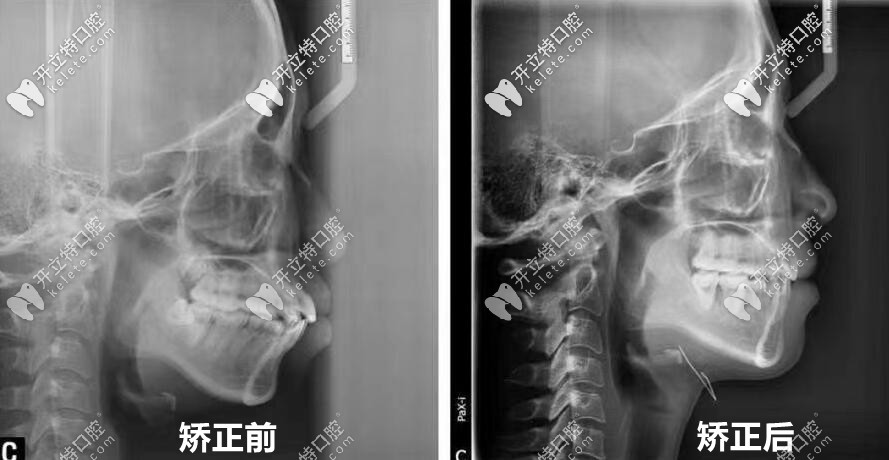

▼正畸前后全牙和頭顱側(cè)位片▼

00后妹子:正畸前后全牙和頭顱側(cè)位片對(duì)比